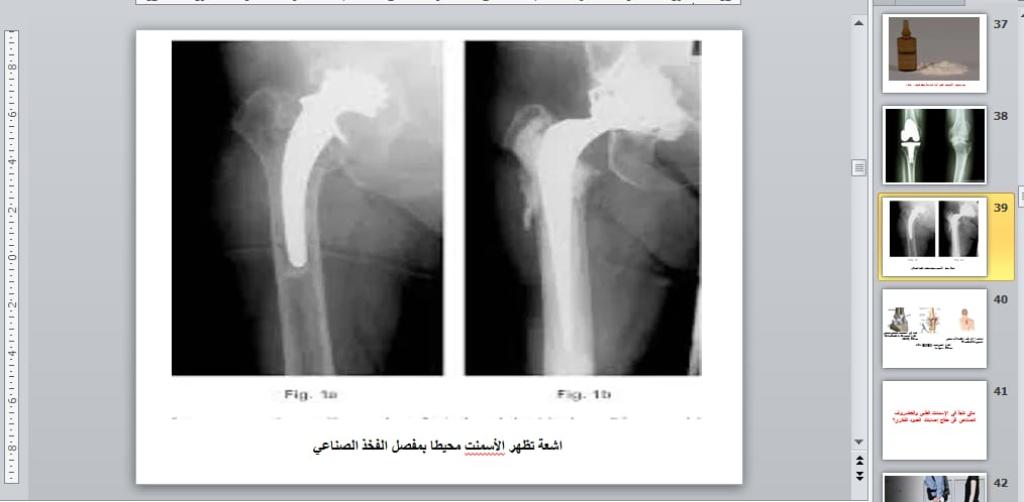

برعاية السيد رئيس جامعة الموصل الأستاذ الدكتور قصي كمال الدين الاحمدي وبإشراف السيدة عميد كلية العلوم الأستاذ الدكتورة هيام عادل إبراهيم وضمن نشاطات التعليم المستمر في كليتنا ، أقيمت في قسم الفيزياء الطبية دورة علمية عبر الفضاء الإلكتروني بعنوان ” الاسمنت الطبي في مفهوم الفيزياء الطبية ” للفترة 3 – 5 كانون الثاني 2023 .تضمنت محاضرات اليوم الأول التي القاها أ.م.د. قصي خطاب عمر الاسمنت الطبي كعلاج فقرات العمود الفقري ، الاسمنت الطبي يستخدم في جراحة المفاصل و هشاشة العظام ، الاسمنت العظمي العلاج الأمثل لآلام المفاصل بدون جراحة فضلاً عن الاسمنت العظمي مكوناته وخواصه الفيزيائية .بينما تطرّق في اليوم الثاني عن تشخيص الاسمنت الطبي بكل أنواعه باستخدام عدة تقنيات منها ( باستخدام الأشعة السينية التقليدية ، باستخدام جهاز CT scan ، باستخدام الرنين المغناطيسي ، باستخدام جهاز PET المسح البوزتروني ) .وفي اليوم الثالث والأخير القى م.د. محمود أحمد محمد فخري محاضرة عن بعض خواص الاسمنت الطبي وطرق تحضيره سريراً ، ومدى تأثر التركيب النهائي له بطرق التحضير الآنية ، وماهي فائدة بعض الاضافات لتركيبة الاسمنت الطبي ، كما تضمنت المحاضرة حقنة الاسمنت الطبي لمعالج كسور الفقرات الناتجة عن هشاشة العظام بالدرجة الأولى أو بعض الحوادث أو الأمراض الأخرى المؤدية إلى ضعف الفقرات وظهور هذه الكسور.شعبة الإعلام والعلاقات العامةالجمعة 6 كانون الثاني 2023